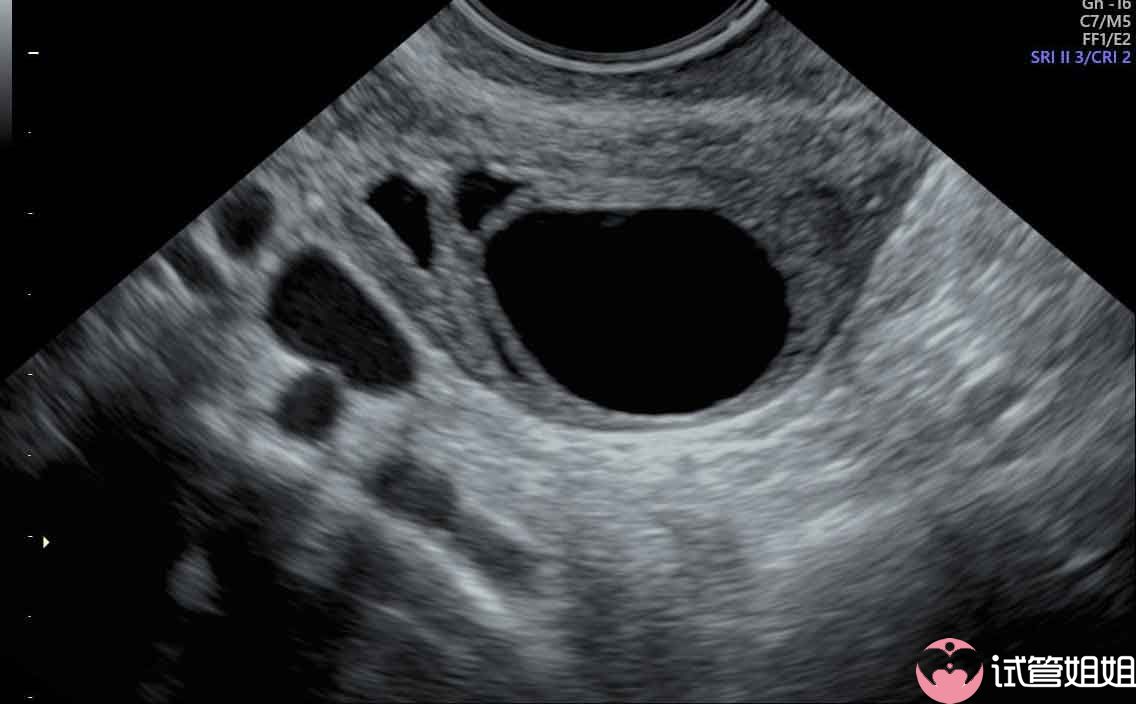

一、什么是三代试管婴儿促排?三代试管婴儿促排,即第三代试管婴儿技术中的一种辅助生殖技术。它通过使用促性腺激素(GnRH)来刺激卵巢,促使卵泡生长和发育,从而提高卵子的数量和质量。这种方法可以有效地解决一些女性因为卵巢功能不足或者排卵障碍导致的不孕问题。二、三代试管婴儿促排对身体有伤害吗?1. 取卵过程可能会疼痛:在促排过程中,医生会通过穿刺的方式取出多个卵泡,这个过程可能会有一定的疼痛感。

但是,随着医学技术的不断进步,这种疼痛已经得到了很好的控制,很多患者都可以忍受。此外,医生会在取卵前给予局部麻醉,以减轻疼痛。2. 卵巢过度刺激综合症的风险:虽然促排可以提高卵子的数量和质量,但过度刺激卵巢可能导致卵巢过度刺激综合症(OHSS)。OHSS是一种严重的并发症,表现为腹胀、腹痛、恶心、呼吸困难等症状。然而,目前临床上已经可以通过调整促排药物的剂量和监测患者的卵巢反应来降低OHSS的风险。